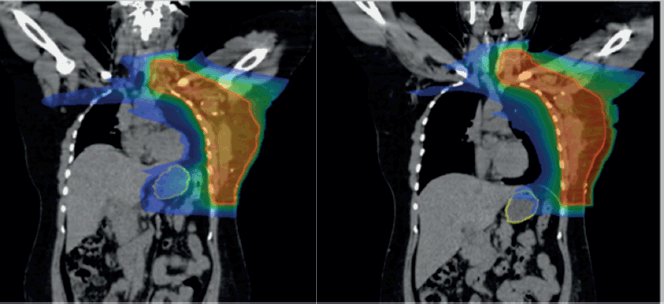

Overall, the significant factors influencing acute upper GI toxicity included radiation technique, RT dose and dose to stomach (D10 cc, D30 cc and D60 cc). Importantly, left chest wall or breast irradiation with or without RNI during FB was associated with a significantly higher risk of GI toxicity compared to DIBH, which holds a significant negative correlation implying a protective effect and helps in reducing GI toxicity (p = 0.035) (Supplementary

Figures 1a,b and 2a,b). Additionally, a positive correlation was found between larger PTV volume and the risk of developing acute upper GI toxicity (p = 0.036).

Supplementary Figure 2. (a): Coronal view showing stomach position in FB (VMAT), (b): In DIBH (VMAT).